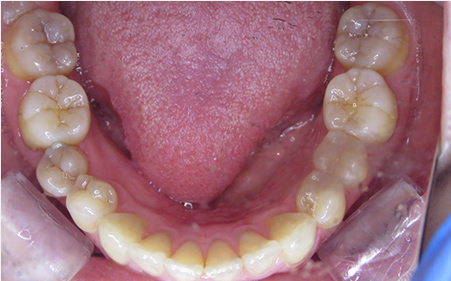

CASE03

Before

After

| 施術名 |

インビザラインGoを用いた矯正治療(叢生) |

| 治療期間 |

6ヶ月 |

| 治療費 |

437,800円(税込) |

| リスク |

マウスピース装置により疼痛・咬合時痛を生じる事があります。割れたり壊れたりする事があります。 |

歯科医師からのコメント

「前歯のねじれとがたつきを治したい」でご来院されました。短期間で矯正治療が終わったので、とても喜んでおられました。矯正治療後も定期検診いらっしゃって歯並びを維持しておられます。